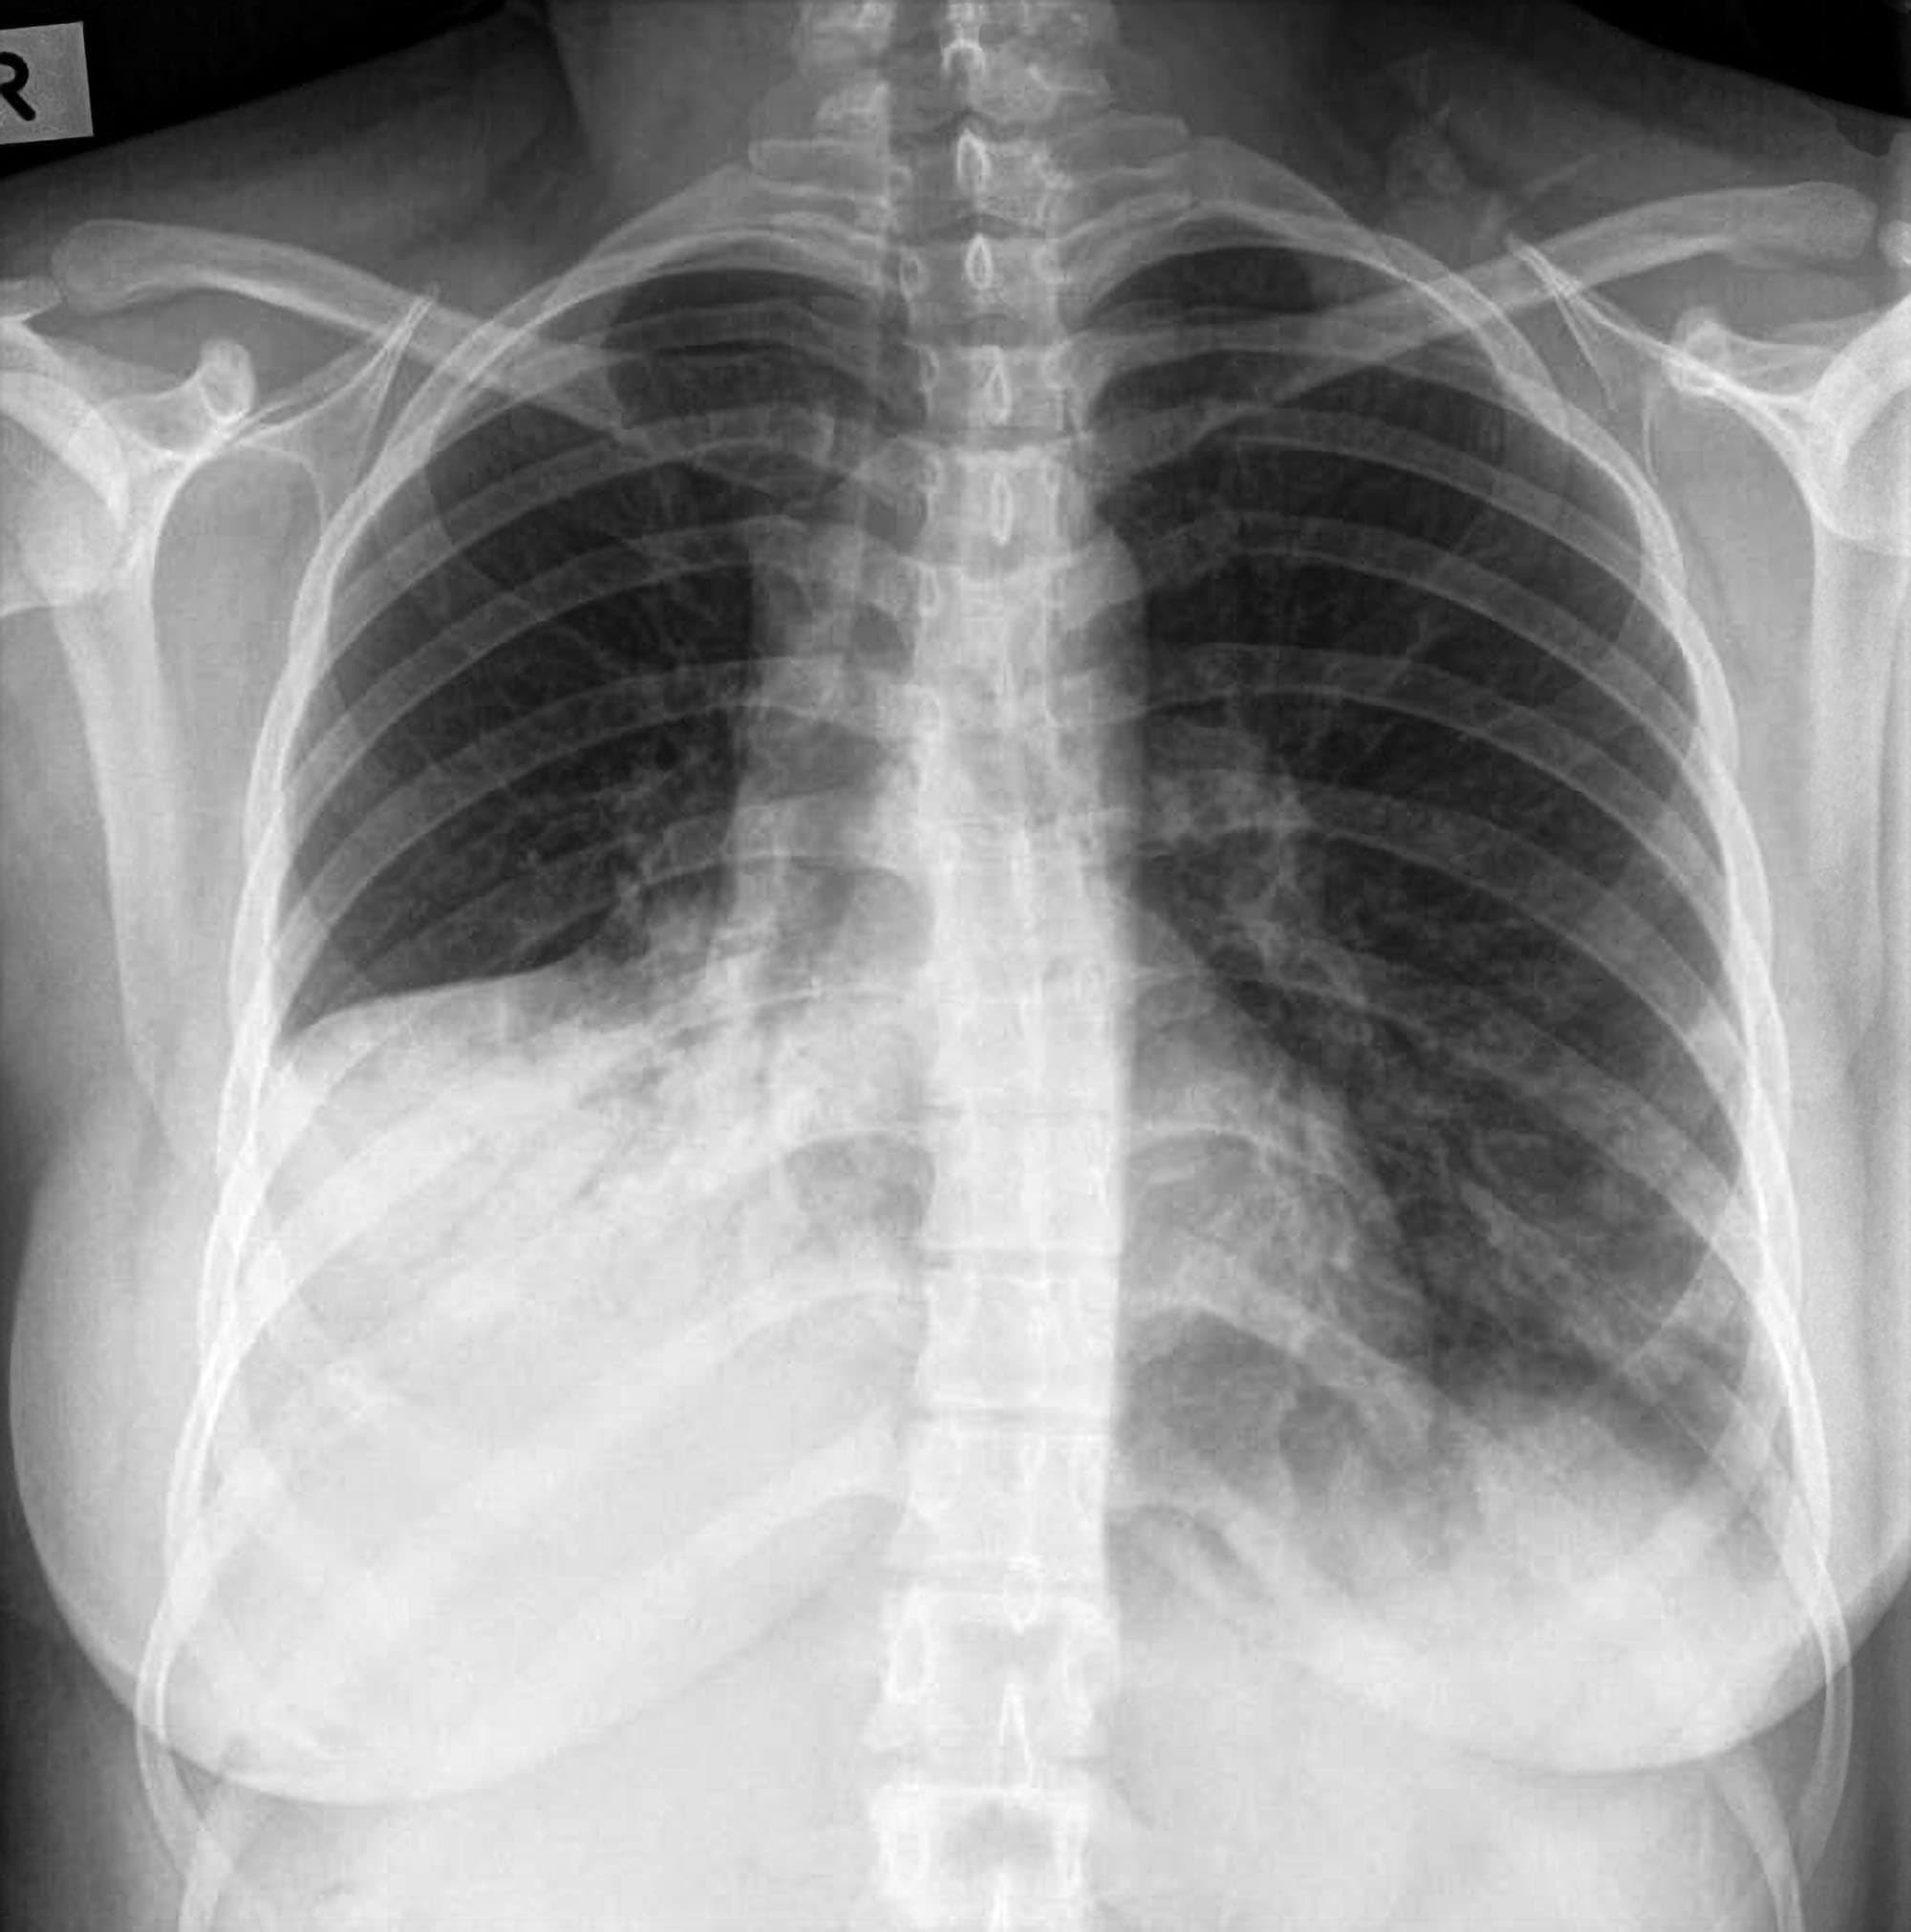

There are several ways to diagnose lung consolidation. A chest X-ray is often the first test ordered, as it can help to identify the location and extent of the consolidation. A CT scan may also be ordered if more detailed imaging is needed. In some cases, a lung biopsy may be necessary to confirm the diagnosis.